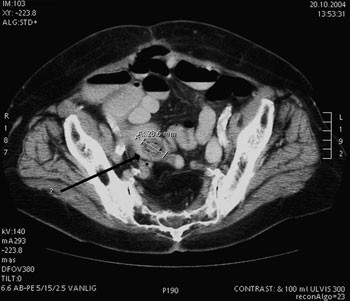

Gastroskopi viste normale funn i oesophagus, ventrikkel og duodenum. CT abdomen og bekken viste et sentralt midtlinjebrokk som inneholdt tynntarm. Det var flere små væskenivåer i tynntarmen og tykktarmen helt ned til endetarmen. Verken tynntarm eller tykktarm var utvidet. I tarmene, «mest sannsynlig i coecum», ble det beskrevet «et ovalt formet ca. 2,8 x 2 cm stort legeme» (fig 1). Dette inneholdt ikke kalk, og var kun synlig som en defekt i kontrasten. Det var ikke påvisbare ekspansive eller infiltrative prosesser. Det var ingen påvisbar irritasjon i buken og ikke fri væske. Noen dager senere viste ny røntgen tarmpassasje lett til moderat utvidede tynntarmer fylt med kontrast 3 timer etter kontrasttilførsel. Først etter 17 timer hadde kontrasten passert over i en normalt vid tykktarm og rectum. Utvidelsen i proksimale tynntarm var da gått tilbake, og tynntarmen var gassfylt bare i lett grad.

CT var hos vår pasient ikke diagnostisk. Det var ikke luft i galleveiene, og gallesteinen inneholdt ikke kalk. Dermed var den kun synlig på CT som en defekt i kontrasten. Det var ikke mulig å si hva denne representerte, og lokaliseringen ble feilaktig antatt å være i coecum. Ved ettergransking er steinen også synlig som en kontrastdefekt i tynntarmen på passasjebildene (fig 2). Både CT og den første kontrastundersøkelsen av passasjen underestimerte utvidelsen av tynntarmen.